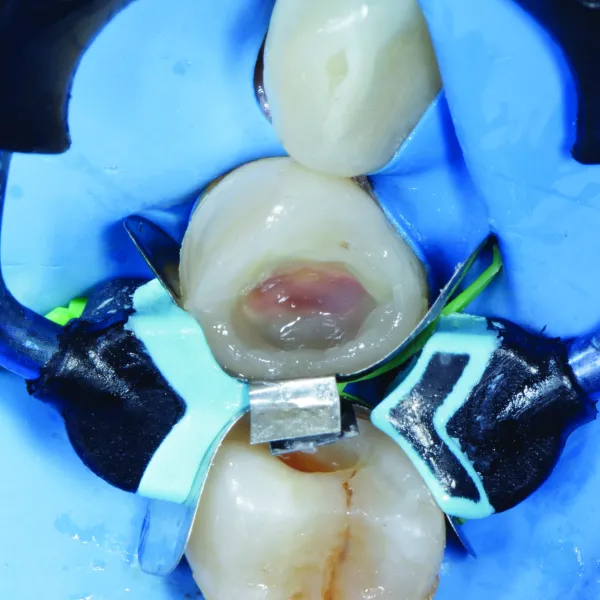

Figure 1: Class II defect (mesial) tooth #45 and #46 with suspected distal Class II defect on tooth #45. Tooth #44 shows discoloration beneath the existing Class II composite restoration, with weak and unsupported walls.Figure 2: Multiple Class II defects. #44 shows underline decay; #45 mesial/distal Class II defect, and #46 mesial defect.Figure 3: Caries end point removal, achieving peripheral seal zone and removing unsupported enamel. The picture was taken after air abrasion and selective etching was performed. Garrison® Quad Matrix System™ large wedge was placed as prewedging to protect rubber dam.